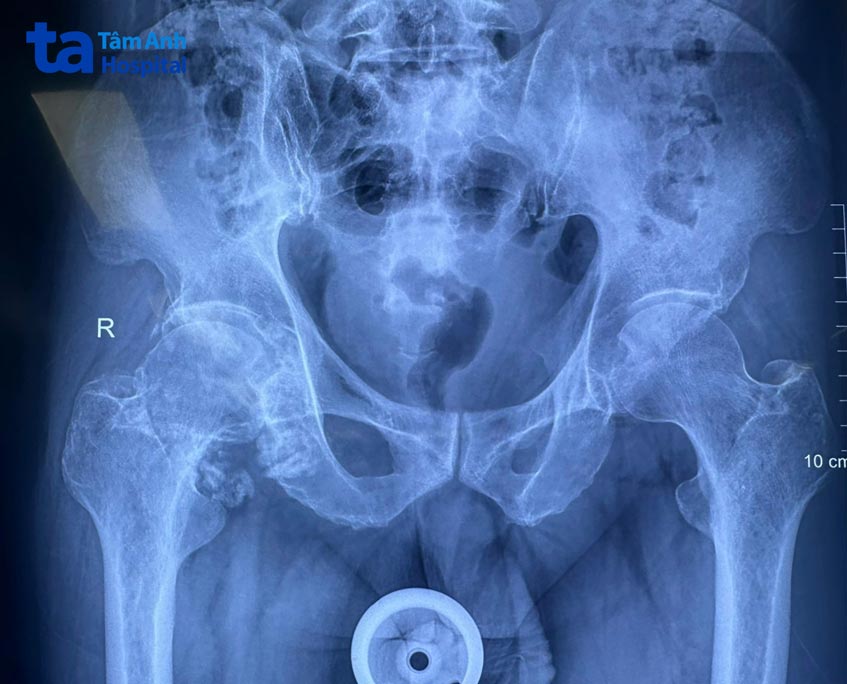

Trực tiếp thăm khám và điều trị cho ông Hiếu là ThS.BS.CKI Lê Đình Khoa. Thông qua kết quả chụp MRI và Xquang, bác sĩ Khoa nhận định ông Hiếu mắc bệnh lý u sụn màng hoạt dịch khớp tại khớp háng. Xung quanh khớp háng của người bệnh xuất hiện rất nhiều u sụn, thậm chí có hạt kẹt vào giữa khớp háng, dẫn đến thoái hóa khớp háng. Đây chính là nguyên gây đau đớn nghiêm trọng, làm người bệnh không thể đi lại hoặc thực hiện các động tác liên quan đến khớp háng.

Thông thường, đối với những trường hợp u sụn có số lượng hạt sụn ít, chưa gây thoái hóa khớp, người bệnh sẽ được nội soi loại bỏ u sụn. Tuy nhiên, ở trường hợp của ông Hiếu, sau 4 năm chịu đựng, bệnh đã phát triển nghiêm trọng, buộc phải mổ mở để loại bỏ toàn bộ u sụn và thay khớp háng. Bác sĩ Khoa cho biết, mục tiêu điều trị là lấy lại tầm vận động cho khớp và ngăn bệnh tái phát. Ca phẫu thuật được thực hiện theo 3 bước: lấy tất cả hạt u sụn ra, loại bỏ hoàn toàn màng hoạt dịch và thay khớp nhân tạo.